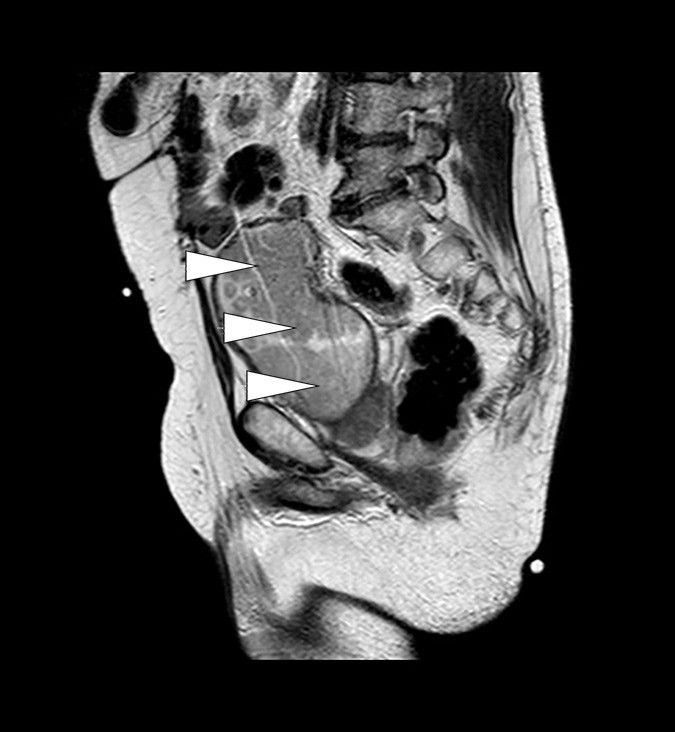

Like etter innleggelse ble det tatt CT urinveier uten intravenøs kontrast (fig 1). Denne viste bilateral uttalt hydronefrose og hydroureter med moderat atrofi av nyreparenkym. Det var forstørret urinblære med høyattenuerende innhold som ved blod. Cystoskopi ble gjort akutt og viste at blæren var fylt av koagler og papillomatøse tumorforandringer. Disse ble biopsert. Hematurikateter og bilaterale nefrostomikatetre ble anlagt. Biopsiene viste høygradig urotelialt karsinom, pT1GIII. Det ble ikke sett muskulatur. MR bekken viste uttalte tumorforandringer i nærmest hele blæren med innvekst i prostata og begge urinledere. Den viste også gjennombrudd av muscularis propria som ved minst T3-stadiet med muskelinvasiv blærecancer (fig 2, fig 3). For øvrig var det normale funn uten organmetastaser eller forstørrede lymfeknuter. Skjelettscintigrafi viste ikke tegn til metastaser. Ved nevropsykologisk testing fant man en sannsynlig mild kognitiv svik som ble planlagt fulgt opp etter utskrivning. Nyrefunksjonen bedret seg noe ved hjelp av avlastningen, og kreatininverdien stabiliserte seg rundt 190 μmol/l.